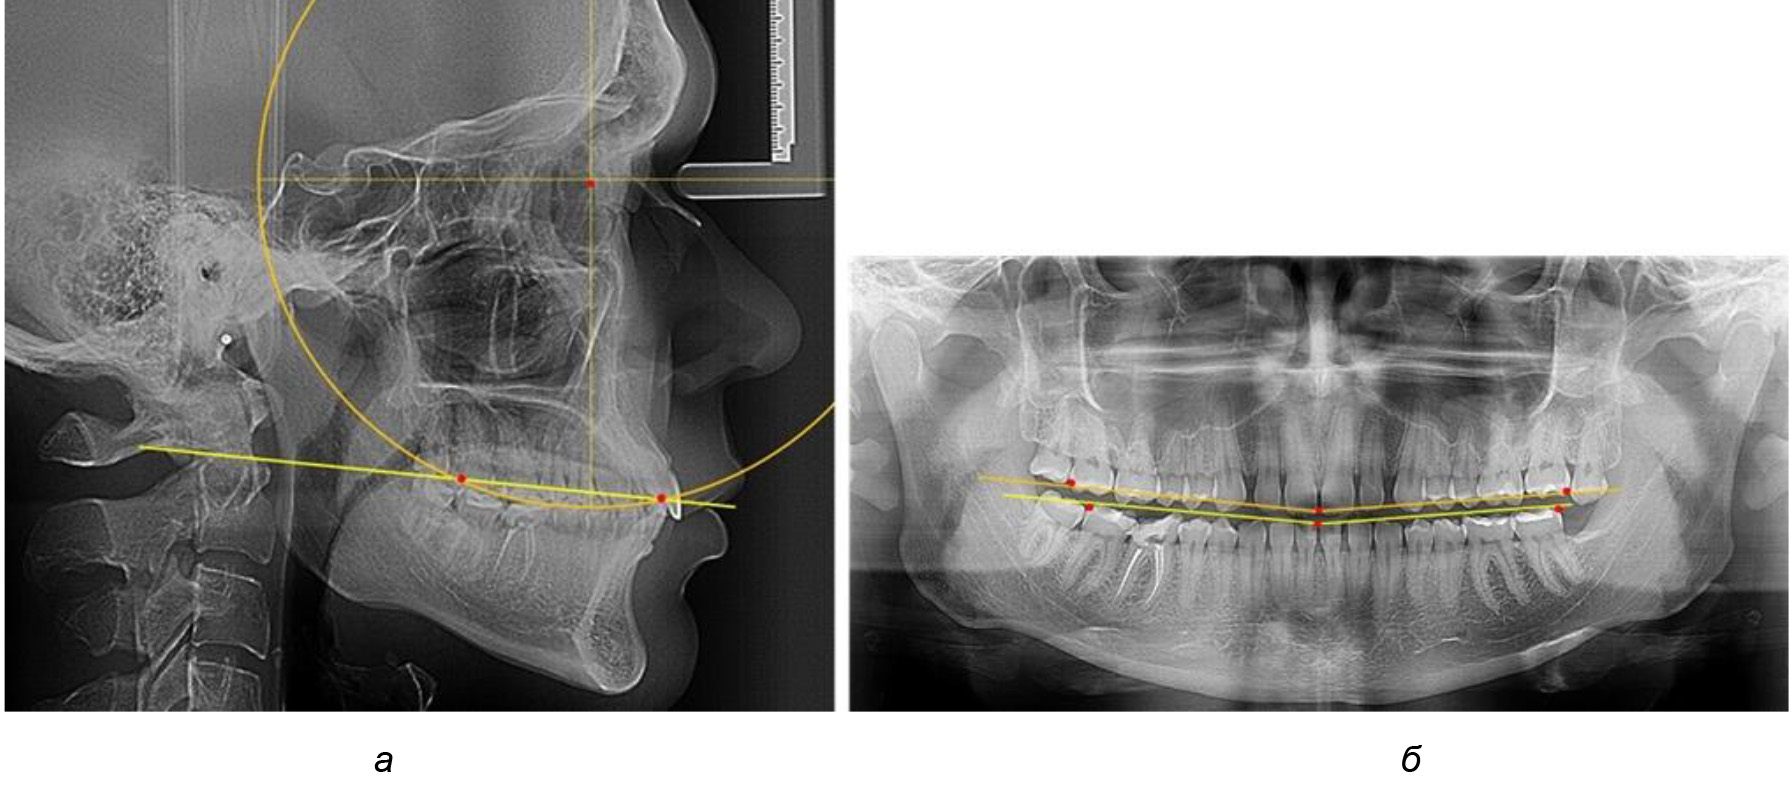

Во 2-й подгруппе 2-й группы было обследовано 7 человек.

Указанная величина не имела достоверного отличия с 1-й подгруппой (р ˃ 0,05), что определяло однородность групп по количественному признаку.

Обращает на себя внимание, что глубина кривой Spee в анализируемой подгруппе практически не отличалась от показателей, полученных у людей с физиологической окклюзией, и составляла (4,23 ± 1,58) мм. Отношение радиуса окружности к сагиттальному размеру окклюзионной линии в среднем по подгруппе составляло 1,623 ± 0,02 и соответствовало числу Фибоначчи.

После лечения пациентов техникой «прямой» дуги, так же как и в 1-й подгруппе, было отмечено увеличение сагиттального размера окклюзионной лини в среднем на (2,38 ± 0,83) мм. Окклюзионная линия практически касалась окклюзионного контура всех жевательных зубов, и отмечалось практически полное отсутствие кривой Spee, так же как и у людей 1-й подгруппы 2-й группы (рис. 6).

Рис. 6. Особенности ТРГ при оптимальной кривой Spee до лечения (а) и после лечения (б) техникой «прямой» дуги

Таким образом, проведенное лечение техникой «прямой» дуги способствует нормализации окклюзионного равновесия и торку передних зубов, однако не соответствует оптимальному окклюзионному статусу, характеризующему физиологическую окклюзию. При этом величина нижнечелюстного угла оставалась на прежнем уровне.